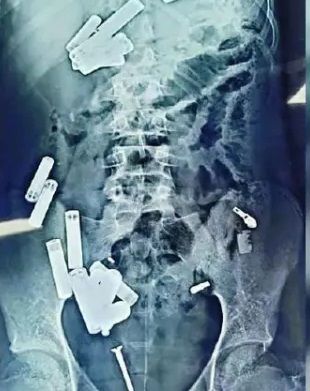

Лікарі дістали з тіла хлопчика 56 металевих предметів / Фото: Rare Shot News

В Індії 15-річний хлопчик помер після того, як лікарі видалили з його живота 56 сторонніх предметів – зокрема, батарейки, ланцюжки, уламки бритви та гвинти.

Адітья Шарма з міста Хаттрас, штат Уттар-Прадеш, помер після того, як медики лікарні Сафдарджунг у Делі провели складну п'ятигодинну операцію з видалення цих предметів.

Під час операції були видалені предмети вагою 350 грамів. Але, як повідомляється, інфекція поширилася на його кишківник, що призвело до його розриву.

Попри наявність предметів у шлунку, в горлі та роті хлопчика не було жодних ознак пошкоджень.